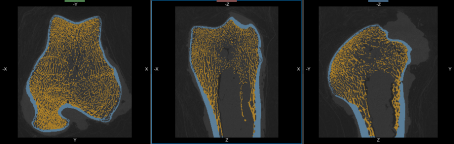

The output of this process is a filled region of interest, which is an input for separating cortical and trabecular bone.

and a filled region of interest in which the holes of the bone segmentation are closed.

Region of interest (Filled)… The segmentation of the filled area corresponding to the bone cortex and the marrow.

Segmentation of the cortical and trabecular bone is the most critical step for the accurate quantification of selected morphometric indices. Two methods — Kohler and Buie — are available for segmenting cortical and trabecular bone. The input of the automated segmentation is a bone segmentation in which bone mineralization is present (see Performing Initial Bone Segmentations) and a filled region of interest in which the bone segmentation are filled. The output of the process is two regions of interest listed below:

Cortical bone… The intersection of the cortical area with the input bone segmentation.

Trabecular bone… The intersection of the trabecular area with the input bone segmentation.

At the end of the process, two new regions of interest — Cortical bone and Trabecular bone — appear in the Data Properties and Settings panel.